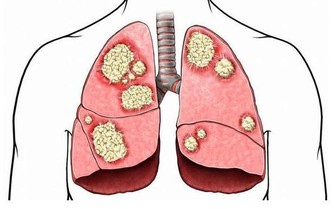

糖尿病是一種慢性進行性疾病,患者不是不能有更長的壽命,但這要求他們必須花更多時間來對付並發症。並不是說所有糖尿病患者都注定會出現並發症,而是說,你必須防止問題出現。

長期高血糖會對身體的許多器官造成傷害,但積極改變生活方式有助於降低血糖和預防糖尿病並發症。採取行動永遠不會太晚,即使你已經患有糖尿病很多年,仍然可以做出改變以改善健康狀況。

糖尿病患者經常表示他們感覺血糖不高。結果,他們決定不治療自己的糖尿病。這非常危險。未經治療的糖尿病可能導致不可逆的並發症。因而,從一開始就認真對待糖尿病很重要。